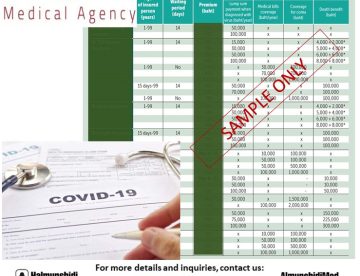

COVID19 Insurance Plans: Everyone is excited to travel after they have been fully vaccinated. One…